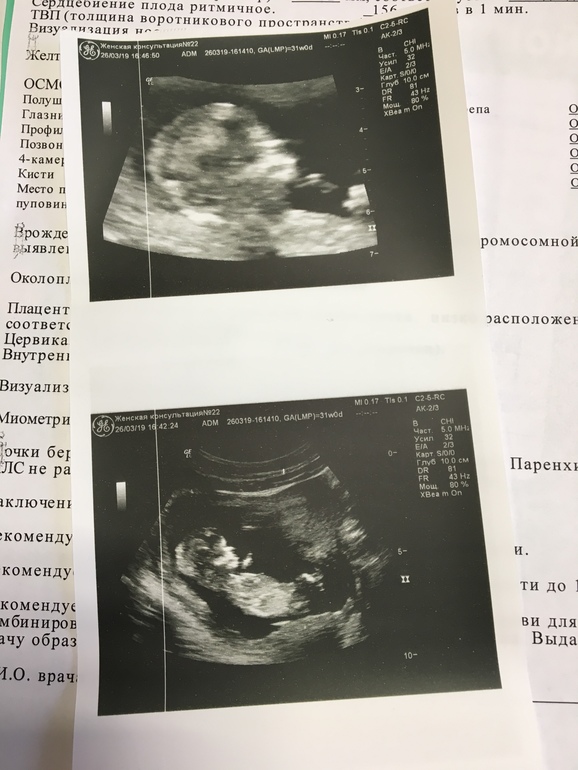

Ура!!! Вчера прошли первый скрининг, все хорошо!))) Крошка моя большая, по КТР опережаем на неделю (72мм). Боже, как подумаю о том, что внутри меня сидит уже 7-ми сантиметровый человечек, так сразу слезы умиления)))))

Сказали, что пока больше похоже на девочку, но еще рано утверждать) Но я почему-то с самого начала чувствовала, что это девочка)